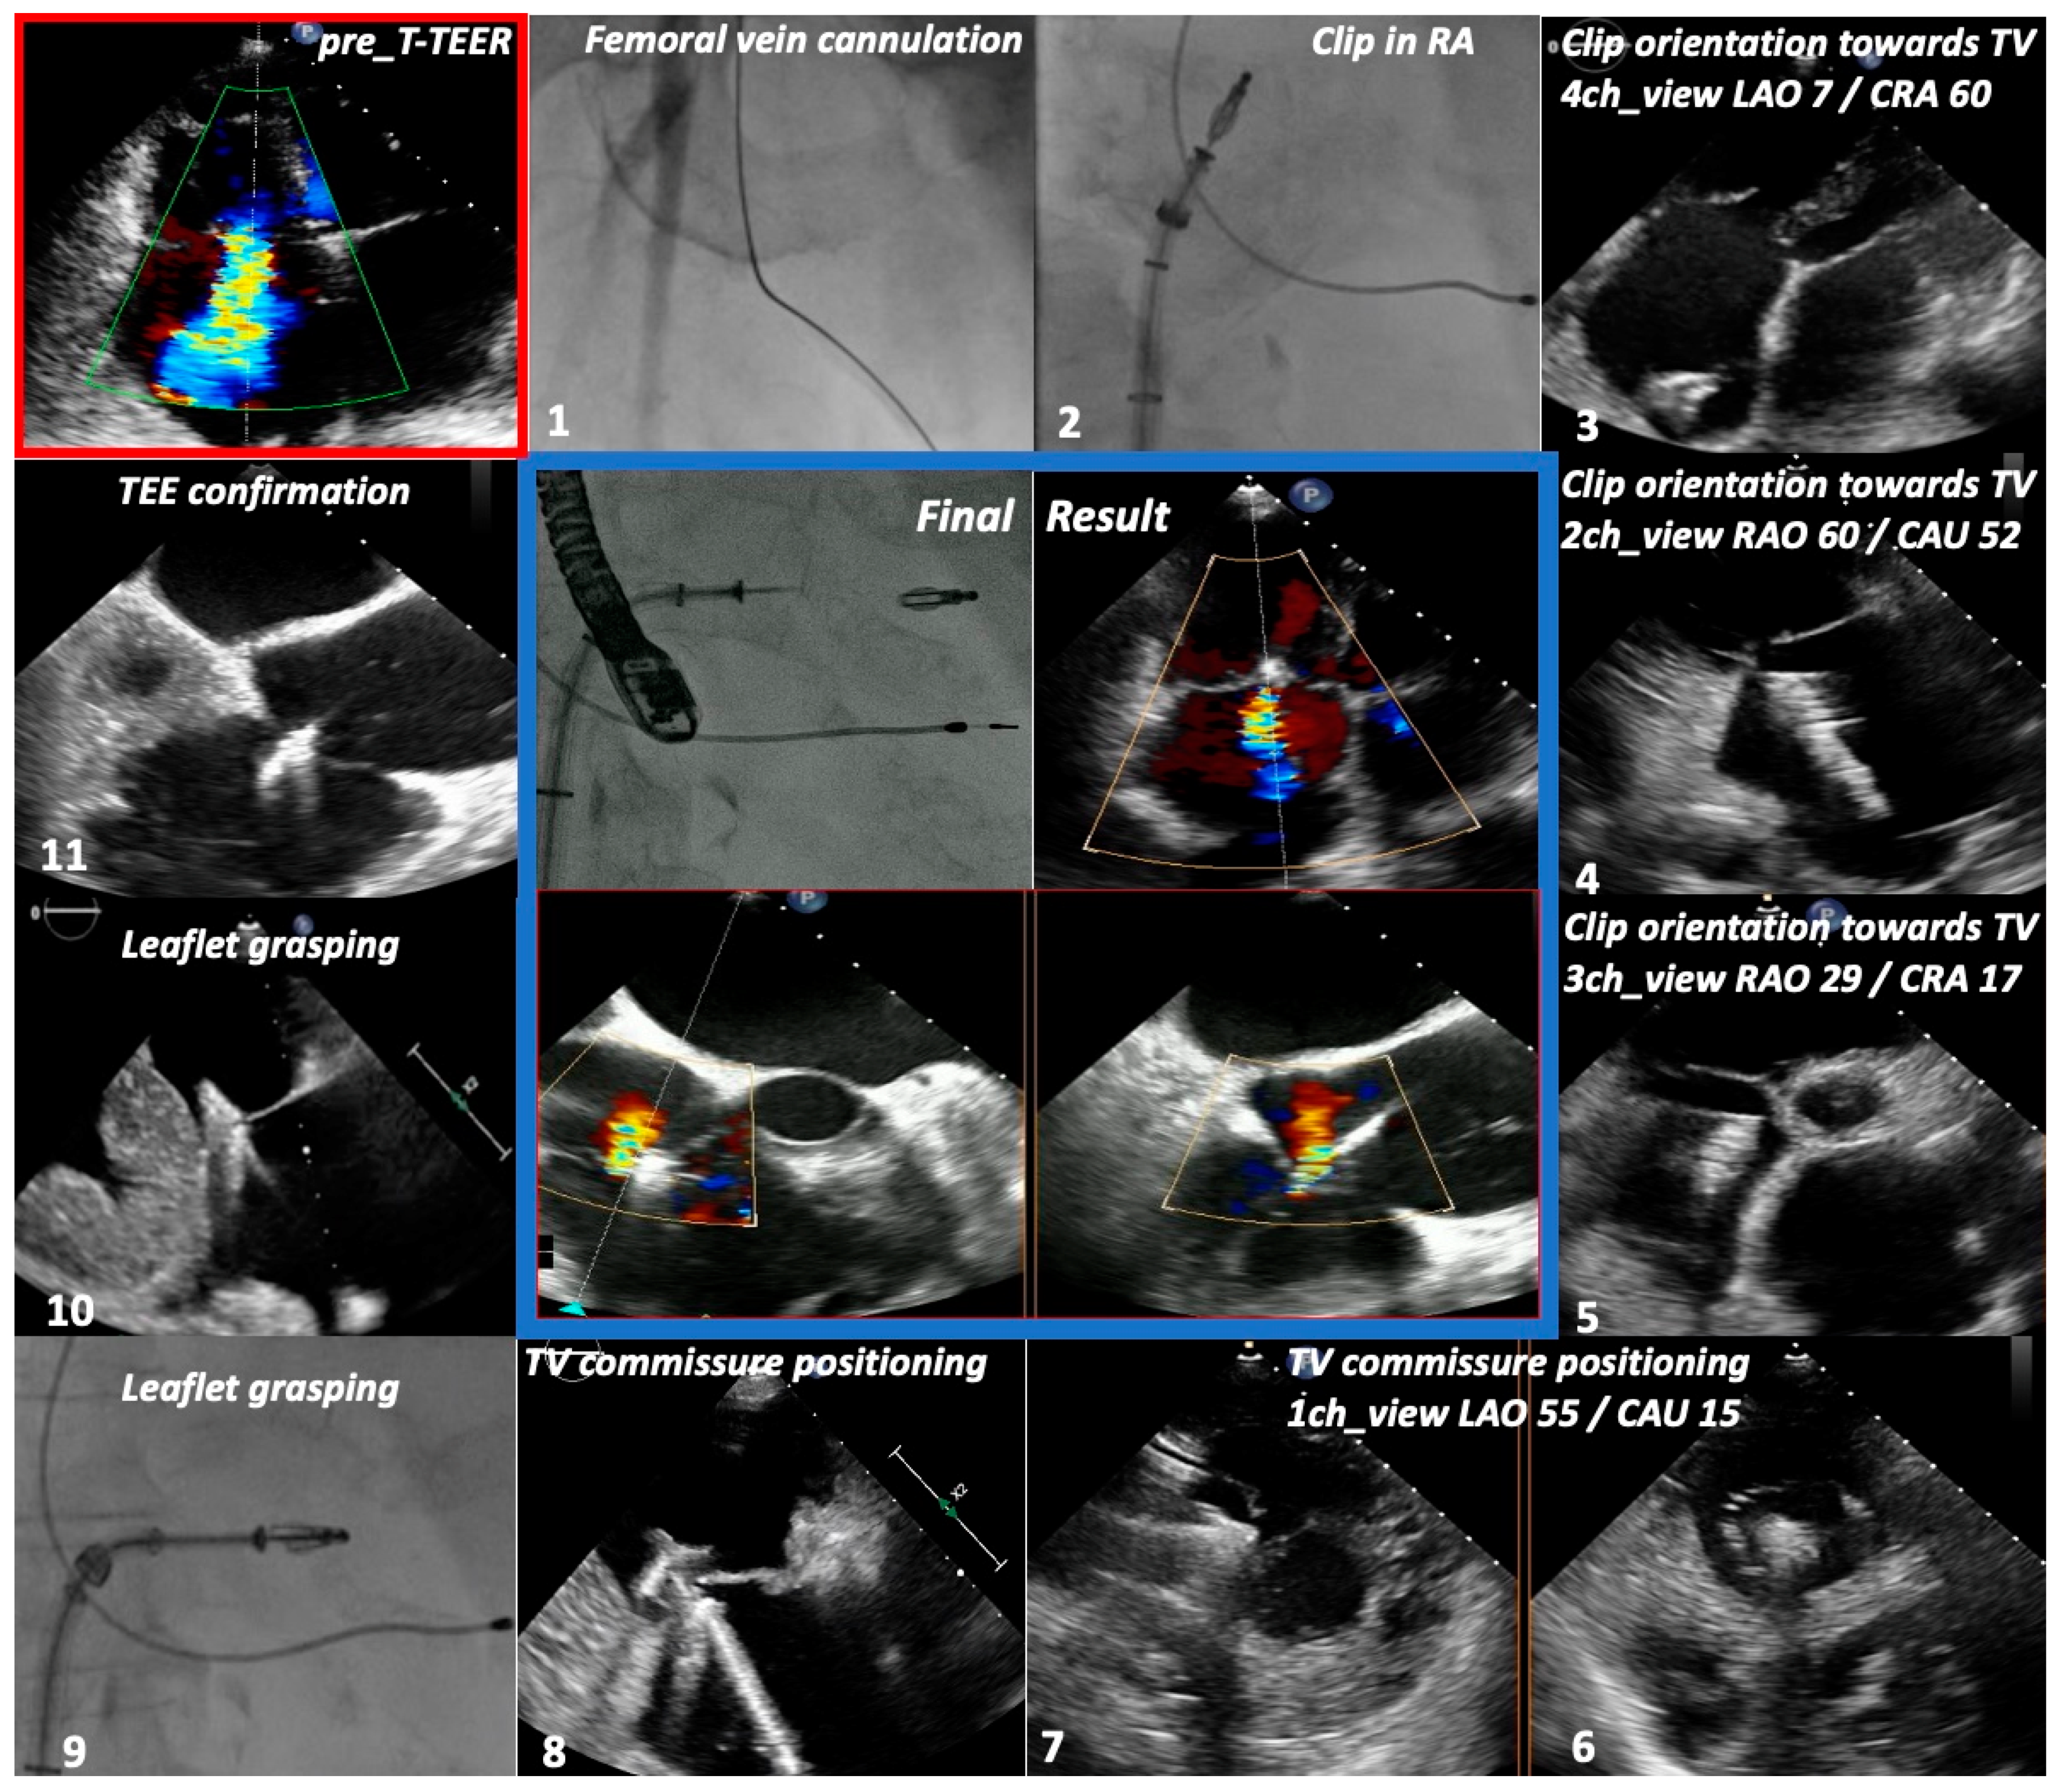

2.4. Imaging Protocol

2.5. Procedural Protocol